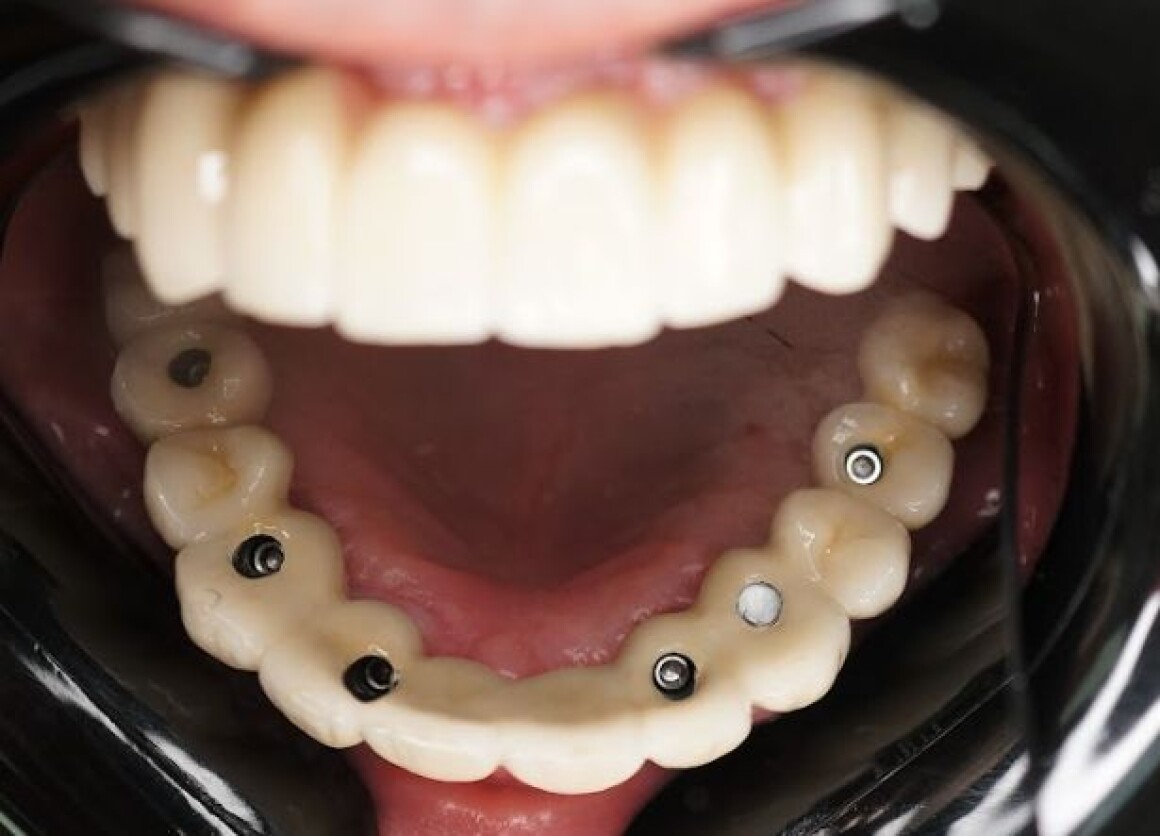

• Имплантация 12 имплантантов за один раз

• Установка временных коронок на имплантантах